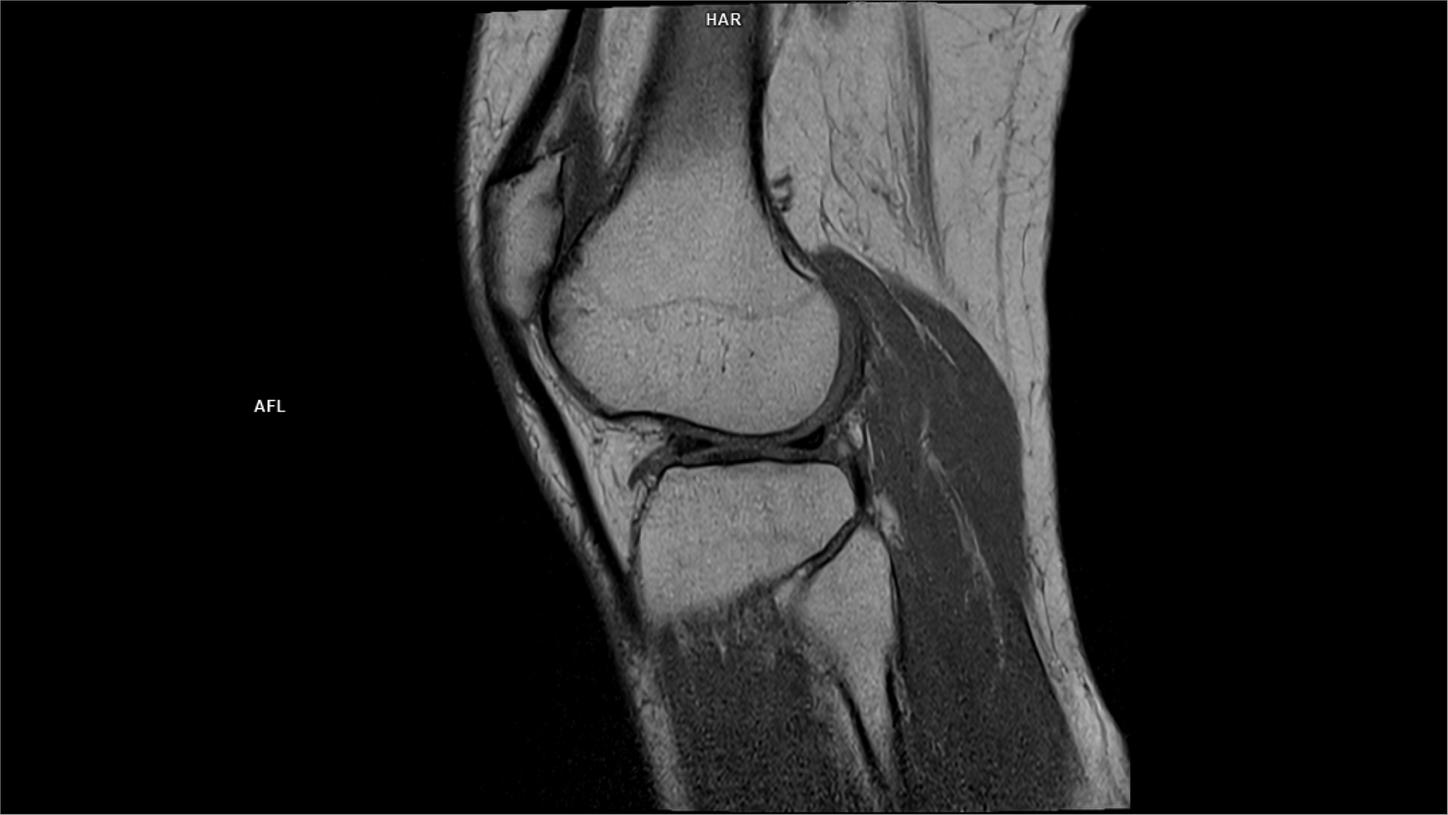

Sagittal T1-MAGNETOM Free.Max

04/07/2022

Coil-Contour Small x2/Resolution-672/Scan Time-3:49/Aceleration-p2 DRS